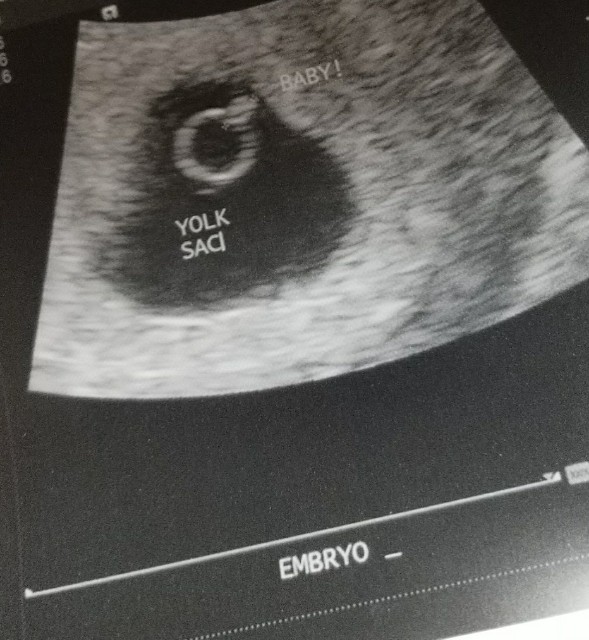

5 weeks 4 days pregnant ultrasound pictures

5 weeks and 4 days pregnant – Baby Fetal Progress, Ultrasound …

5 Week Ultrasound Pictures : 5 week ultrasound and high hcg …

5 Week Ultrasound Pictures : What should an ultrasound show at 5 weeks …

5 weeks 5 days ultrasound – Glow Community

Hoping for Baby B: 5 week ultrasound

Does this ultrasound look normal for 5 weeks 6 days? Read description …

5 weeks and 6 days pregnant – Baby Fetal Progress, Ultrasound …

5 1 2 Weeks Pregnant Ultrasound Pictures – PictureMeta

sonogram 5 weeks

sonogram 5 weeks

5 Weeks – The Maternity Gallery

5 weeks 4 days pregnant ultrasound pictures at